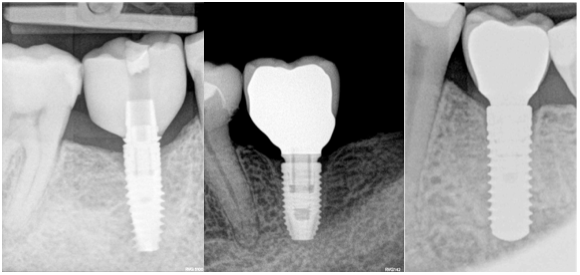

The first thought, which enters the mind, just places implant deeper subcrestally (Fig 5). Firstly, there must be enough place for the alveolar nerve that the implant could be positioned subcrestally in a safe manner.

It is advised that the implant would stop at least 1 mm over the nerve. Subcrestal placement is suggested to cause controlled bone remodeling, but not a bone loss. It is interesting to note, that not all implants can be placed subcrestally. In addition, implant-abutment connection stability becomes very important, if located subcrestally.